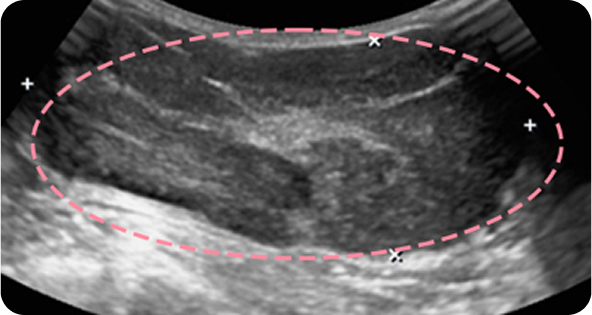

외국에서 내원한 17세 환자분은 빠르게 자라는 큰 유방 종양으로 대학병원 수술이 권고되었으나, 고난도 시술 경험을 바탕으로 3차례 맘모톰을 통해 성공적으로 제거했습니다. 흉터를 걱정했던 환자와 보호자 모두 결과에 만족하며, 현재까지 정기 추적검사에서 깨끗한 상태를 유지하고 있습니다.